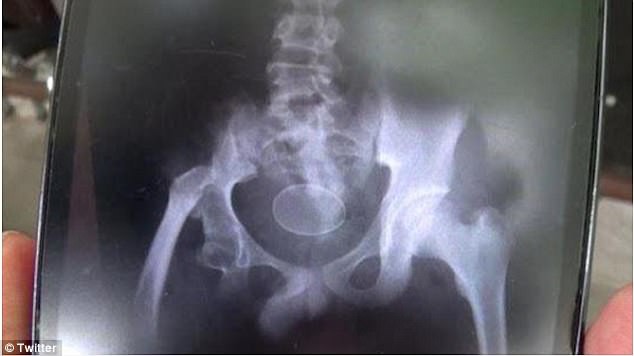

![]() |

Hình chụp X-Quang cậu bé Akmal. |